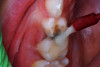

(1.) Hypocalcified/carious first molar, 12 months after SDF application.

Figure 1

SDF was developed in Osaka, Japan, in 1969.24,25 During the next 5 decades, its use and related research spread around the world.26-32 Various formulations of SDF (Bioride®, Densply Industria e Comericio Ltda; e-SDF, Kids-e-Dental Llp; Riva Star, SDI; Saforide®, Toyo Seiyaku Kasei Ltd) have been developed in different countries to attenuate dental caries infections. In 2014, an SDF solution made up of 62% water, 25% silver, 8% ammonia, and 5% fluoride (Advantage Arrest® Silver Diamine Fluoride 38%, Elevate Oral Care, LLC) was the first to gain approval by the US Food and Drug Administration to be used in the United States as a tooth desensitizing agent33; however, others have since been cleared as well. Its ability to affect dental caries pathodynamics has developed into an exceedingly popular off-label use by dentist clinicians. Figure 1 depicts an example of a malformed and carious permanent first molar that had been treated with SDF followed by 2.5% sodium fluoride varnish 6 months and 12 months prior when it was only partially erupted. This strategy attenuated the caries infection for over a year, until the patient, an extremely anxious 7-year-old boy, was able to tolerate routine restorative treatment.